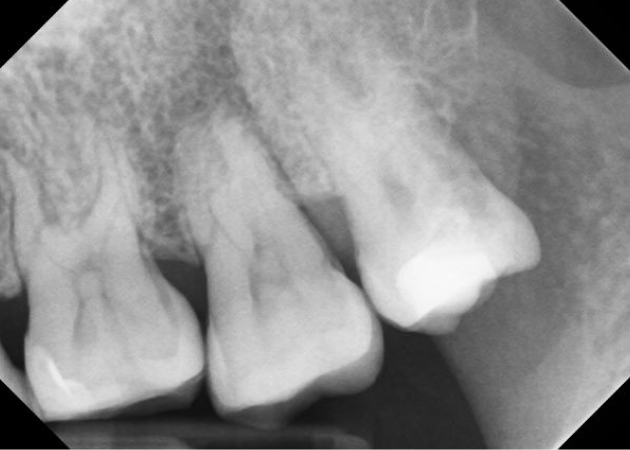

Pre Op #31

Case #1

Patient presented for evaluation of lower right side. Pt reports having pain to biting and chewing.

Tested teeth #’s 30, 31, 31 tested (+)perc, (+)biting, (-)palp, no response to cold.

#31

Periradicular dx: symptomatic apical periodontitis

pulpal dx: necrotic

Treatment : Root canal was completed on tooth # 31, anatomy was funky!